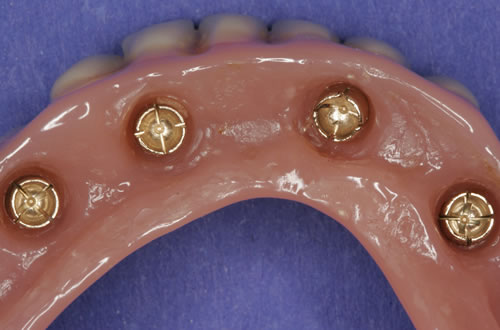

Diese Beispiele ließen sich endlos fortführen. Sie zeigen die Probleme bei der Versorgung zahnloser Kiefer, wie sie immer wieder geschildert werden. Mit Hilfe sehr einfacher Maßnahmen kann durch die Einpflanzung künstlicher Zahnwurzeln eine instabile Prothese soweit befestigt werden, dass die Kau- und Sprechfunktion wieder hergestellt ist. Manchmal kann die alte Prothese weiterverwendet werden, in dem man in die Prothesenbasis Sekundärteile einarbeitet, die für Halt sorgen (Abb. 3.5, 3.6). Bei aufwendigeren Steg- oder Teleskoparbeiten muss auch der Zahnersatz der auf den Implantaten fixiert wird neu angefertigt werden. Diese Arbeiten werden dann brückenartig und sehr grazil gestaltet. (Abb. 3.7 bis 3.12).

Für den zahnlosen Ober- und Unterkiefer werden dies häufiger Stegkonstruktionen oder Teleskopversorgungen sein (Abb. 8.8 bis 8.16).

Auch andere Versorgungsformen sind möglich. So haben sich in bestimmten Fällen Druckknopftechniken wie  Locatoren (Abb. 8.20, 8.21), Kugelknöpfe oder Magnete bewährt. Dabei werden die Implantate mit unterschiedlichen Aufbauten versorgt, wobei jeweils das Sekundärteil in den herausnehmbaren, prothesenähnlichen Teil des Zahnersatzes eingearbeitet wird.